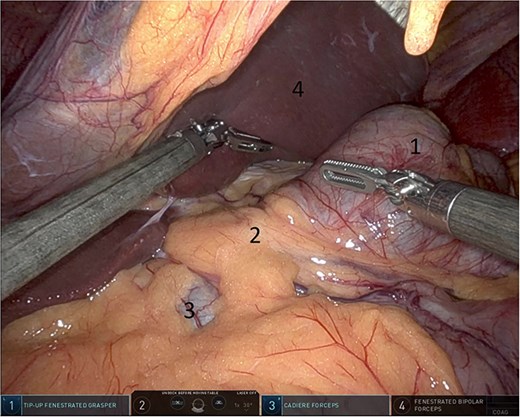

Upon entering the abdominal cavity, dilated bowel loops were observed (Fig. 2), and a significant portion of the colon was found herniated through the foramen of Winslow (Fig. 3). The herniated colon was covered by the pars flaccida (Fig. 4) (Video S1). Careful dissection was performed anterior to the hepatoduodenal ligament (Fig. 5). The gall bladder was retracted to the patient's right upper quadrant, which allowed for the retraction of the foramen of Winslow (Fig. 6) (Video S1). After carefully placing the tip of the instrument posterior to the portal vein and gently elevating it, the herniated colon was successfully reduced (Fig. 7) (Video S1).

Pars flaccida covering the herniated bowel (1: pars flaccida over the herniated bowel, 2: the stomach, 3: transverse colon).